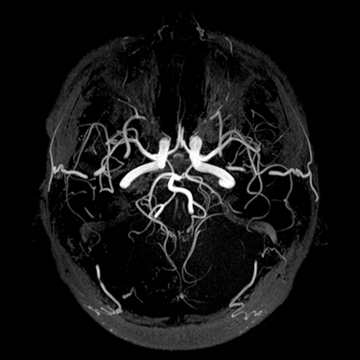

頭部MRA

matrix 320, FOV 220 mm- 頭部MRA